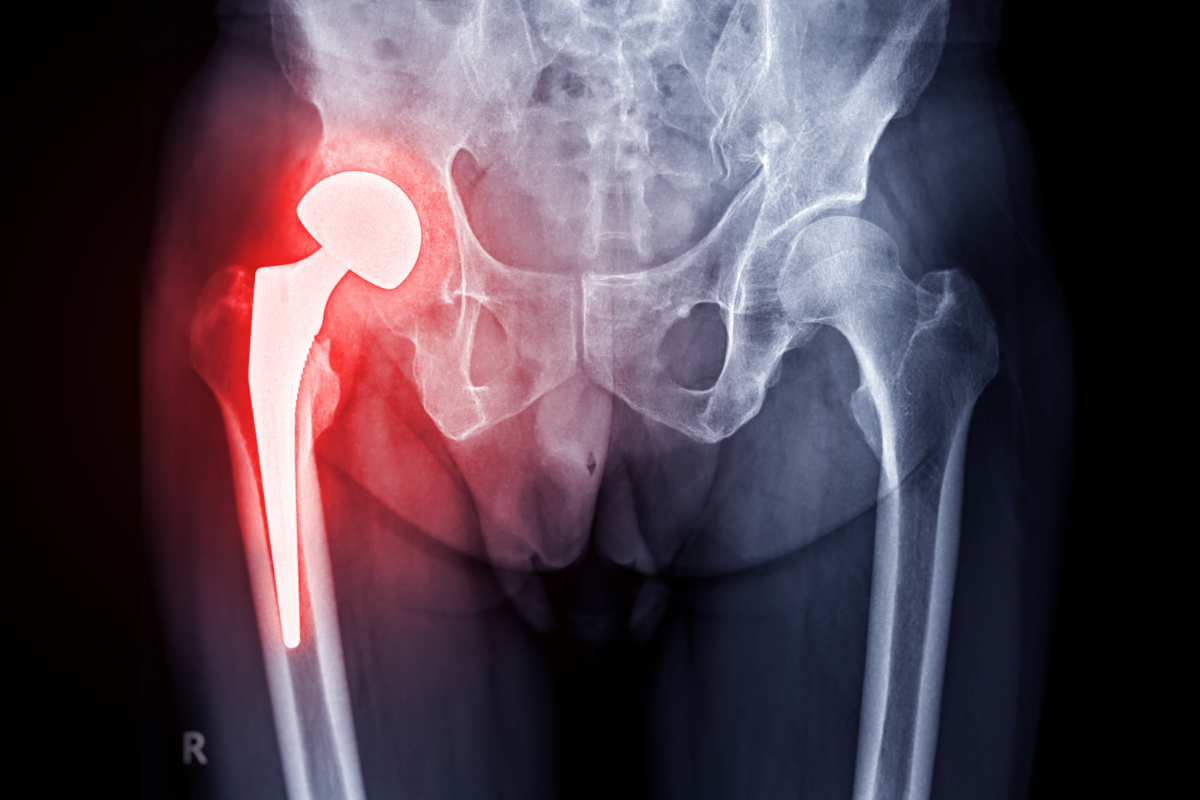

Protezarea șoldului este o intervenție chirurgicală frecvent utilizată pentru a trata durerile severe și limitarea mobilității cauzate de afecțiuni ale șoldului, cum ar fi osteoartrita sau fracturile. Recuperarea postoperatorie este esențială pentru redobândirea mobilității și îmbunătățirea calității vieții, iar kinetoterapia joacă un rol crucial în acest proces. Kinetoterapia nu doar că ajută la reducerea durerii și inflamației, dar contribuie și la restabilirea forței musculare, stabilității și funcționalității șoldului. La KinetikMed din Cluj-Napoca, tratamentele personalizate sunt concepute pentru a sprijini fiecare pacient în procesul de recuperare, oferind soluții eficiente pentru o recuperare completă și rapidă.

Imediat după operația de protezare a șoldului, unul dintre principalele obiective este restabilirea mobilității șoldului. În prima etapă a recuperării, kinetoterapeutul va lucra cu pacientul pentru a îmbunătăți gama de mișcare a articulației șoldului prin exerciții ușoare de mobilizare. Aceste exerciții sunt esențiale pentru prevenirea rigidității și pentru a ajuta pacientul să recupereze mișcările normale ale șoldului. De asemenea, se vor efectua exerciții pentru întinderea mușchilor din jurul șoldului, care pot deveni tensionați sau rigizi după intervenția chirurgicală. Mobilizarea articulației și exercițiile de întindere contribuie la reducerea riscului de formare a țesutului cicatricial și la accelerarea procesului de vindecare.

Un alt aspect esențial al recuperării după protezarea șoldului este întărirea musculaturii care susține articulația șoldului. După intervenția chirurgicală, mușchii din jurul șoldului și ai coapsei pot fi slăbiți, iar întărirea acestora este crucială pentru a restabili stabilitatea articulației și pentru a preveni suprasolicitarea noii proteze. Kinetoterapeutul va ghida pacientul prin exerciții de întărire musculară care vizează mușchii fesieri, ai coapsei și mușchii care sprijină pelvisul. Aceste exerciții ajută la prevenirea durerii, îmbunătățesc mobilitatea și contribuie la menținerea unei posturi corecte.